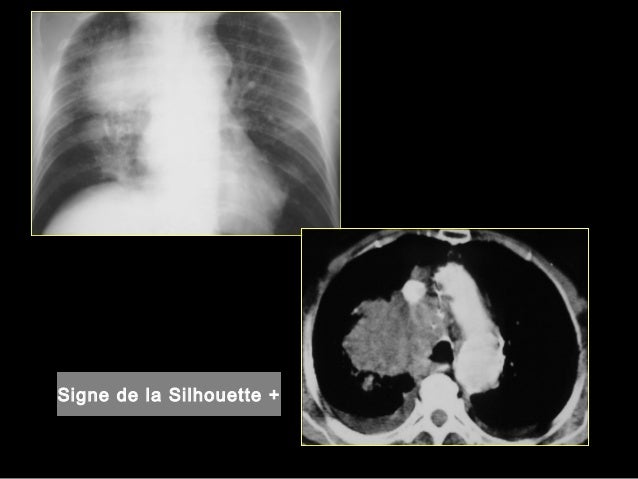

IVVALEUR SEMIOLOGIQUE (4)1 Syndrome de condensation pulmonaire non rétractile 12 causes non infectieuses• cancer bronchopulmonaire• œdème pulmonaire• hémorragies pulmonaires• infarctus pulmonaire consécutif à une embolie pulmonaire 74 IV. / Choir Part Of Rehab For Seniors Who Sing In 'Pulmonaires' Group Choir Part Of Rehab For Seniors Who Sing In 'Pulmonaires' Group A5EC2FD980D85E. Définition Le hile du poumon est l'emplacement des poumons dans lequel les vaisseaux pulmonaires, les nerfs, les vaisseaux lymphatiques et les bronches se rejoignent Les hiles du poumon se situent au niveau du médiastin, qui contient, entre autres, le cœurOn trouve dans les hiles du poumon la veine pulmonaire inférieure, la veine pulmonaire supérieure, le ligament triangulaire, les.

Wisconsin Badger Sports Network is a broadcast radio station in Wisconsin, United States, providing talk and sports programms English;. Rapid Fire Real Estate with Anita Hiles, Jacksonville, Florida 10K likes Anita Hiles is on the air live every Wednesday from 56 pm on WBOB FM 1011 or 600 AM Download the WBOB App!. Généralement l'aspect très central, à partir des hiles pulmonaires qui sont les zones où arrivent et repartent les gros vaisseaux, est associé à des processus non pas pulmonaires directs mais souvent cardiaques avec un retentissement pulmonaire, comme dans l'oedème pulmonaire d'origine cardiogénique.

Semio radio thorax 1 Introduction à la Pathologie Thoracique 2 Les techniques d’imagerie thoracique • Complémentarité 1) par projection Radio graphie conventionnelle 2) Imagerie en coupes Échographie (plèvre, cœur) Scanner / IRM (paroi et cœur) 3) Techniques isotopiques Scintigraphie ventilation/perfusion PET/ tdm (18FDG) 4) Endoscopie bronchique (Anatomie pathologique. At conventional CT, they typically appear as lucent, hypovascular bands;. Cœur droit, de gros hiles pulmonaires et des opacités vasculaires pulmonaires proéminentes L’imagerie de référence de la cardiopathie est l’échocardiographie dont la portabilité, l’absence d’irradiation et la résolution temporelle sont des avantages indéniables dans cette cardiopathie L’imagerie en coupe va trouver.